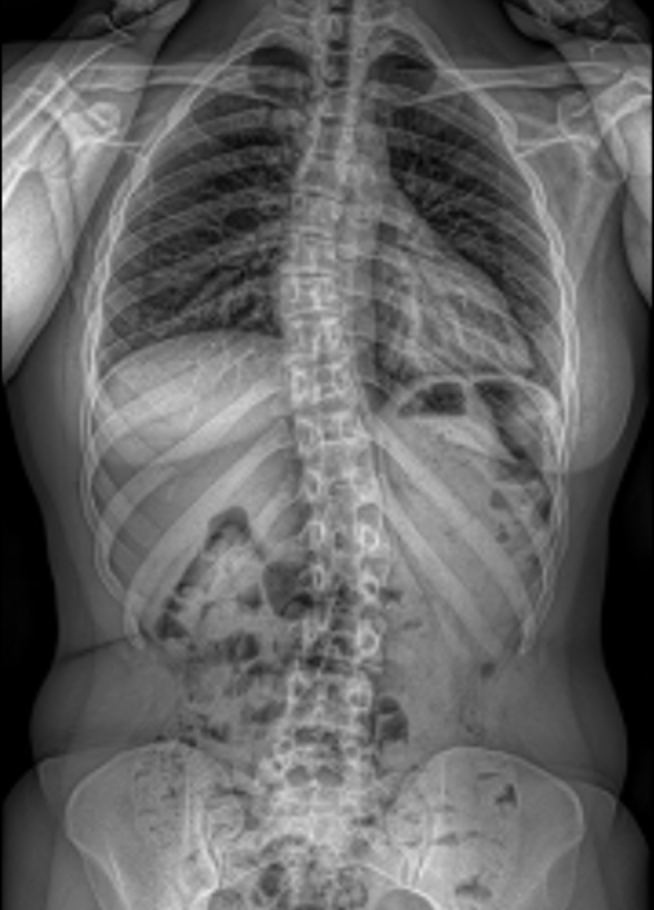

Scoliosis is a condition in which the spine curves sideways rather than growing in a straight line. It most often develops during childhood or adolescence, particularly during growth spurts, but it can also be present in adults. Many people with scoliosis experience no pain or noticeable symptoms, while others may notice pain, uneven shoulders or hips, a visible curve in the back, or clothing that fits unevenly.

Diagnosis is usually made through a physical examination and confirmed with X-rays to measure the spinal curve. Treatment depends on the curve’s size and the patient’s age, ranging from regular monitoring in mild cases to bracing, exercise-based therapy, or surgery for more severe scoliosis. With appropriate care, most patients are able to remain active and live healthy lives.